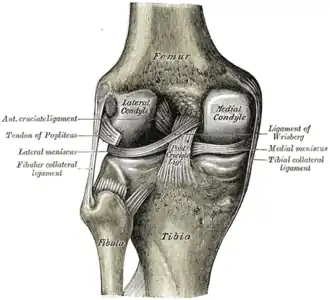

![]() Левый коленный сустав сзади, показаны внутренние связки. | |

- внутрисуставные (крестообразные, поперечная связка колена (между менисками)

Крестообразные связки находятся в полости коленного сустава. К разрывам их приводят запредельные движения в коленном суставе.

- Передняя крестообразная связка (лат. lig. cruciatum anterius) начинается от задневерхней части внутренней поверхности наружного мыщелка (костного выступа) бедренной кости, пересекает полость коленного сустава и прикрепляется к передней части межмыщелкового возвышения большеберцовой кости также в полости сустава. Эта связка стабилизирует коленный сустав и не даёт голени чрезмерно смещаться вперёд, а также удерживает наружный мыщелок большеберцовой кости.

- Задняя крестообразная связка коленного сустава (лат. lig. cruciatum posterius) начинается от передневерхней части боковой поверхности внутреннего мыщелка бедра, пересекает коленный сустав и прикрепляется к наружной части межмыщелкового возвышения большеберцовой кости. Она стабилизирует коленный сустав, и удерживает голень от смещения назад.

Суставные поверхности костей покрыты хрящом. Между сочленяющимися поверхностями бедренной и большеберцовой костей имеются внутренний и наружный мениски, представляющие собой серповидные (формы полулуний) хрящи. Коленный сустав имеет несколько синовиальных сумок: